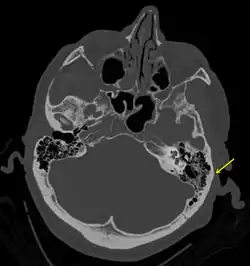

En basisfraktur beskriver et brud på den "underste" del af kraniet – den del af kraniekisten, hjernen kan siges at hvile på. Det er en forholdsvis sjælden fraktur, idet den kun tegner sig for ca. 4% af kraniebrud.[1][2] En basisfraktur er en alvorlig tilstand, idet der er risiko for direkte påvirkning af nærtliggende hjernevæv, ligesom der er risiko for at lædere hjernehinden, så der tabes hjernehindevæske. Dette kan vise sig ved at patienten får et flåd af klar væske fra enten øre eller næse.[3] En basisfraktur vil også kunne medføre en blødning, der viser sig som et brillehæmatom, på engelsk "raccoon eyes", idet blodet kun kan lægge sig i det bløde væv omkring øjnene.

For ukomplicerede basisfrakturer er prognosen oftest god, idet disse kan hele uden yderligere behandling. Patienter med basisfraktur er i høj risiko for at udvikle meningitis.[4] Basisfrakturer er en almindelig dødsårsag i trafikulykker.